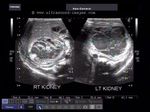

Nephrocalcinosis in neonates

These ultrasound images of neonatal kidneys show- markedly echogenic renal pyramids, bilaterally, with chief involvement of the tips suggestive of medullary nephrocalcinosis. Such nephrocalcinosis in neonates usually follows long term parenteral therapy or due to use of certain drugs notably gentamicin and furosemide. It can also be caused by low fluid intake in the neonate and due to oxygen dependency. This condition, in neonates, usually resolves following correction of the etiological factors. Case courtesy of Joe Antony, MD, India. Images taken using a Toshiba Xario machine.